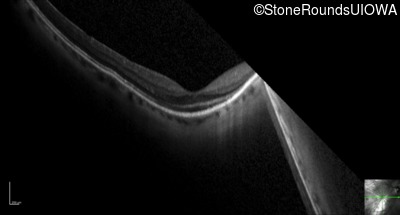

Optical Coherence Tomography - Left - 20/25 +2

Exemplar / OCT Stack

OCT Stack